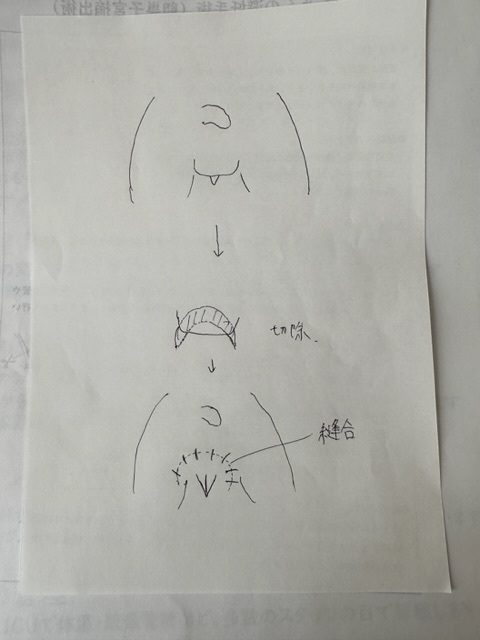

★二分脊椎症、脊椎膜瘤切除手術

(こちらは完了)

CTやMRIによる詳しい検査により

排尿や排便に障害を起こしている為、改善する手術を行う。

手術は予定通り行われました。

引っ張られていた膜瘤を切除

一部骨を削ったそうです。

会陰形成術を11月に予定しております。